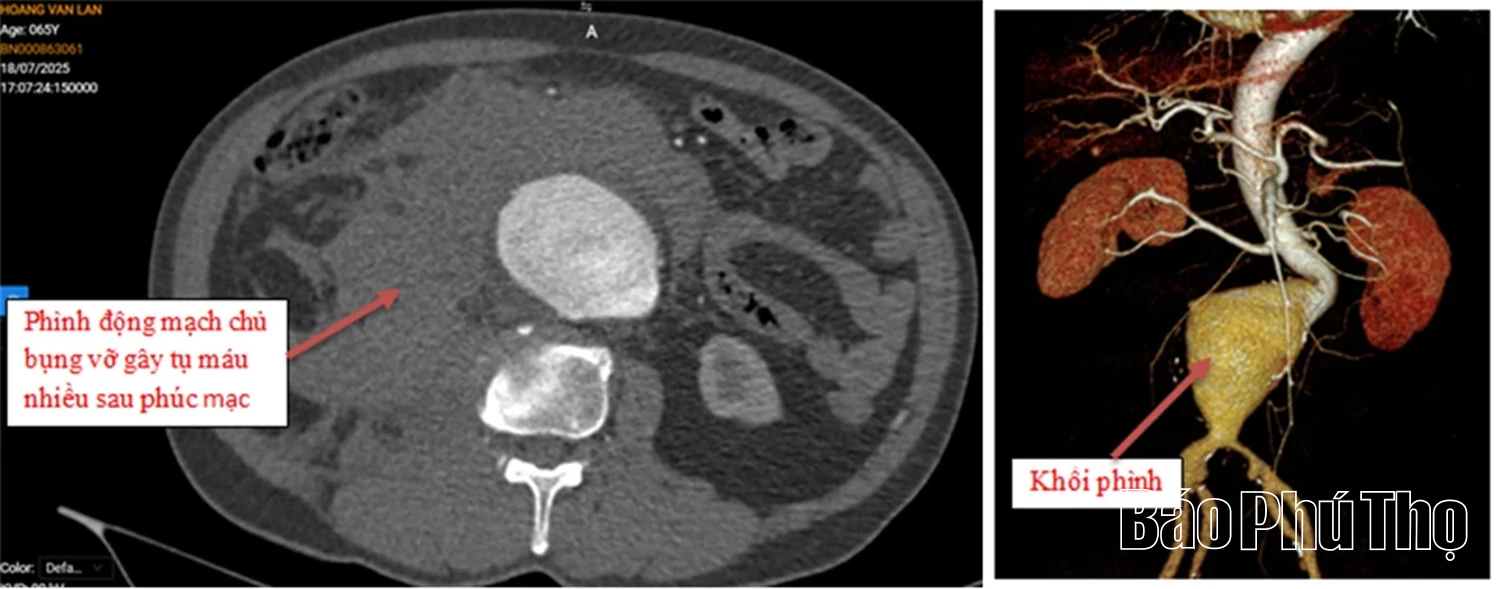

Hình ảnh phim chụp trước phẫu thuật: Phình động mạch chủ bụng vỡ gây tụ máu nhiều sau phúc mạc và hình ảnh khối phình động mạch chủ bụng trước mổ

Tại đây, các bác sĩ đã nhanh chóng khám lâm sàng và chỉ định chụp cắt lớp vi tính đa lát cắt (MSCT) động mạch chủ bụng. Kết quả cho thấy, hình ảnh vỡ phình động mạch chủ bụng, phình hình thoi động mạch chậu chung bên phải và túi phình động mạch chậu chung bên trái. Người bệnh được chẩn đoán vỡ phình động mạch chủ bụng với nhận định có nguy cơ tử vong rất cao.